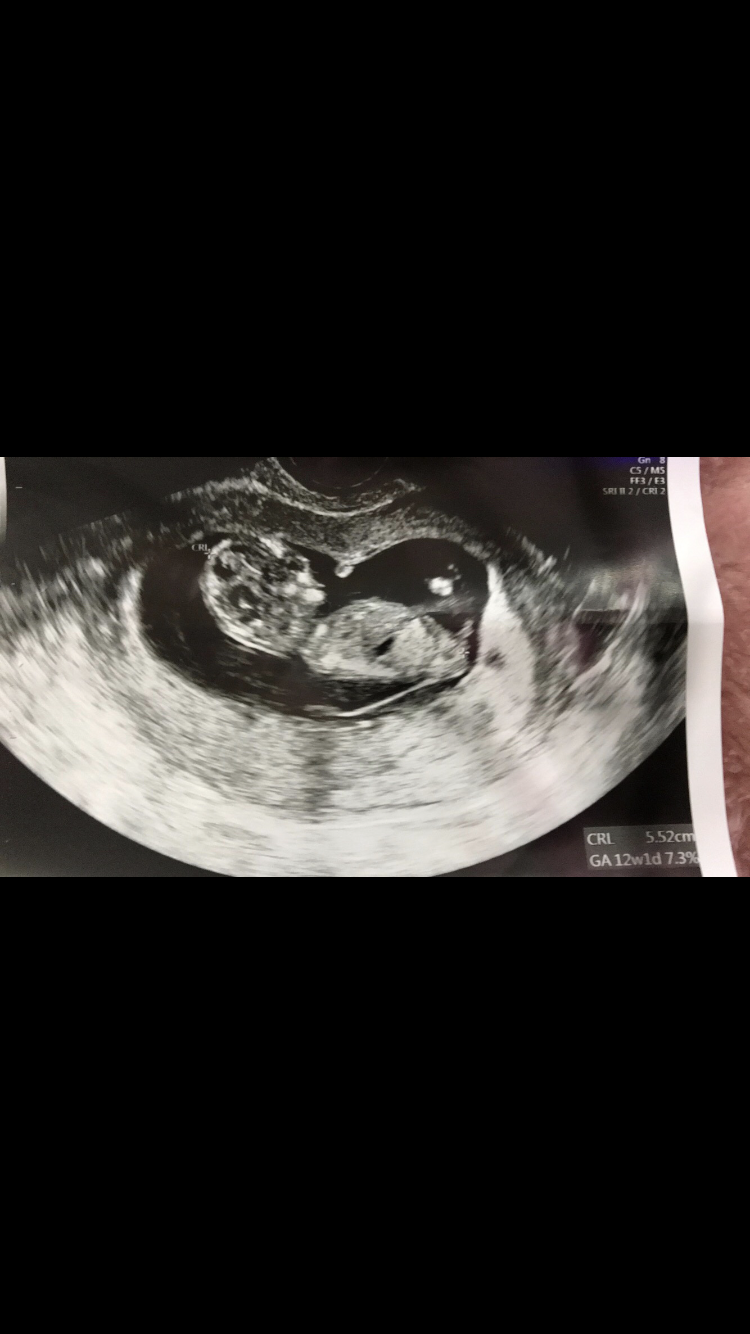

هذه صورة سوناري في الأسبوع ١٢

بان معك الجنس 😻😅 ؟!